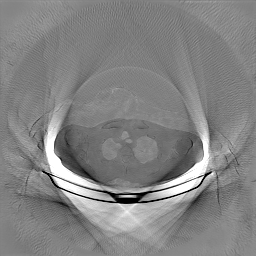

The results for simulated noisy data are shown in Fig. 2. The first and third rows display two representative slices from the test set, and the second and fourth rows present the corresponding error maps. The traditional WCE method suppresses cupping artifacts and recovers some missing anatomical structures but still shows noticeable deviations from the ground truth. Predictions from the four diffusion-based models demonstrate a markedly improved ability to restore anatomical structures. Among them, cDDPM fails to fully reconstruct the patient bed and retains residual noise in its outputs. This noise is attributable to an incomplete reverse denoising process rather than residual Poisson noise, as evidenced in our noise-free experiments (Fig. 5 in the Appendix). PatchDiffusion, diffusionGAN, and I2SB achieve similar visual quality, with I2SB producing the cleanest and most consistent reconstructions.

Quantitative results in Tab. V further confirm I2SB’s superiority over conventional deep learning methods such as FBPConvNet and Pix2pixGAN across RMSE, PSNR, and SSIM. Compared to other diffusion models—including cDDPM, PatchDiffusion, and cLDM—I2SB delivers higher image quality, while diffusionGAN achieves comparable quantitative performance. However, I2SB demonstrates a significant advantage in inference efficiency, as summarized in Tab. IV.